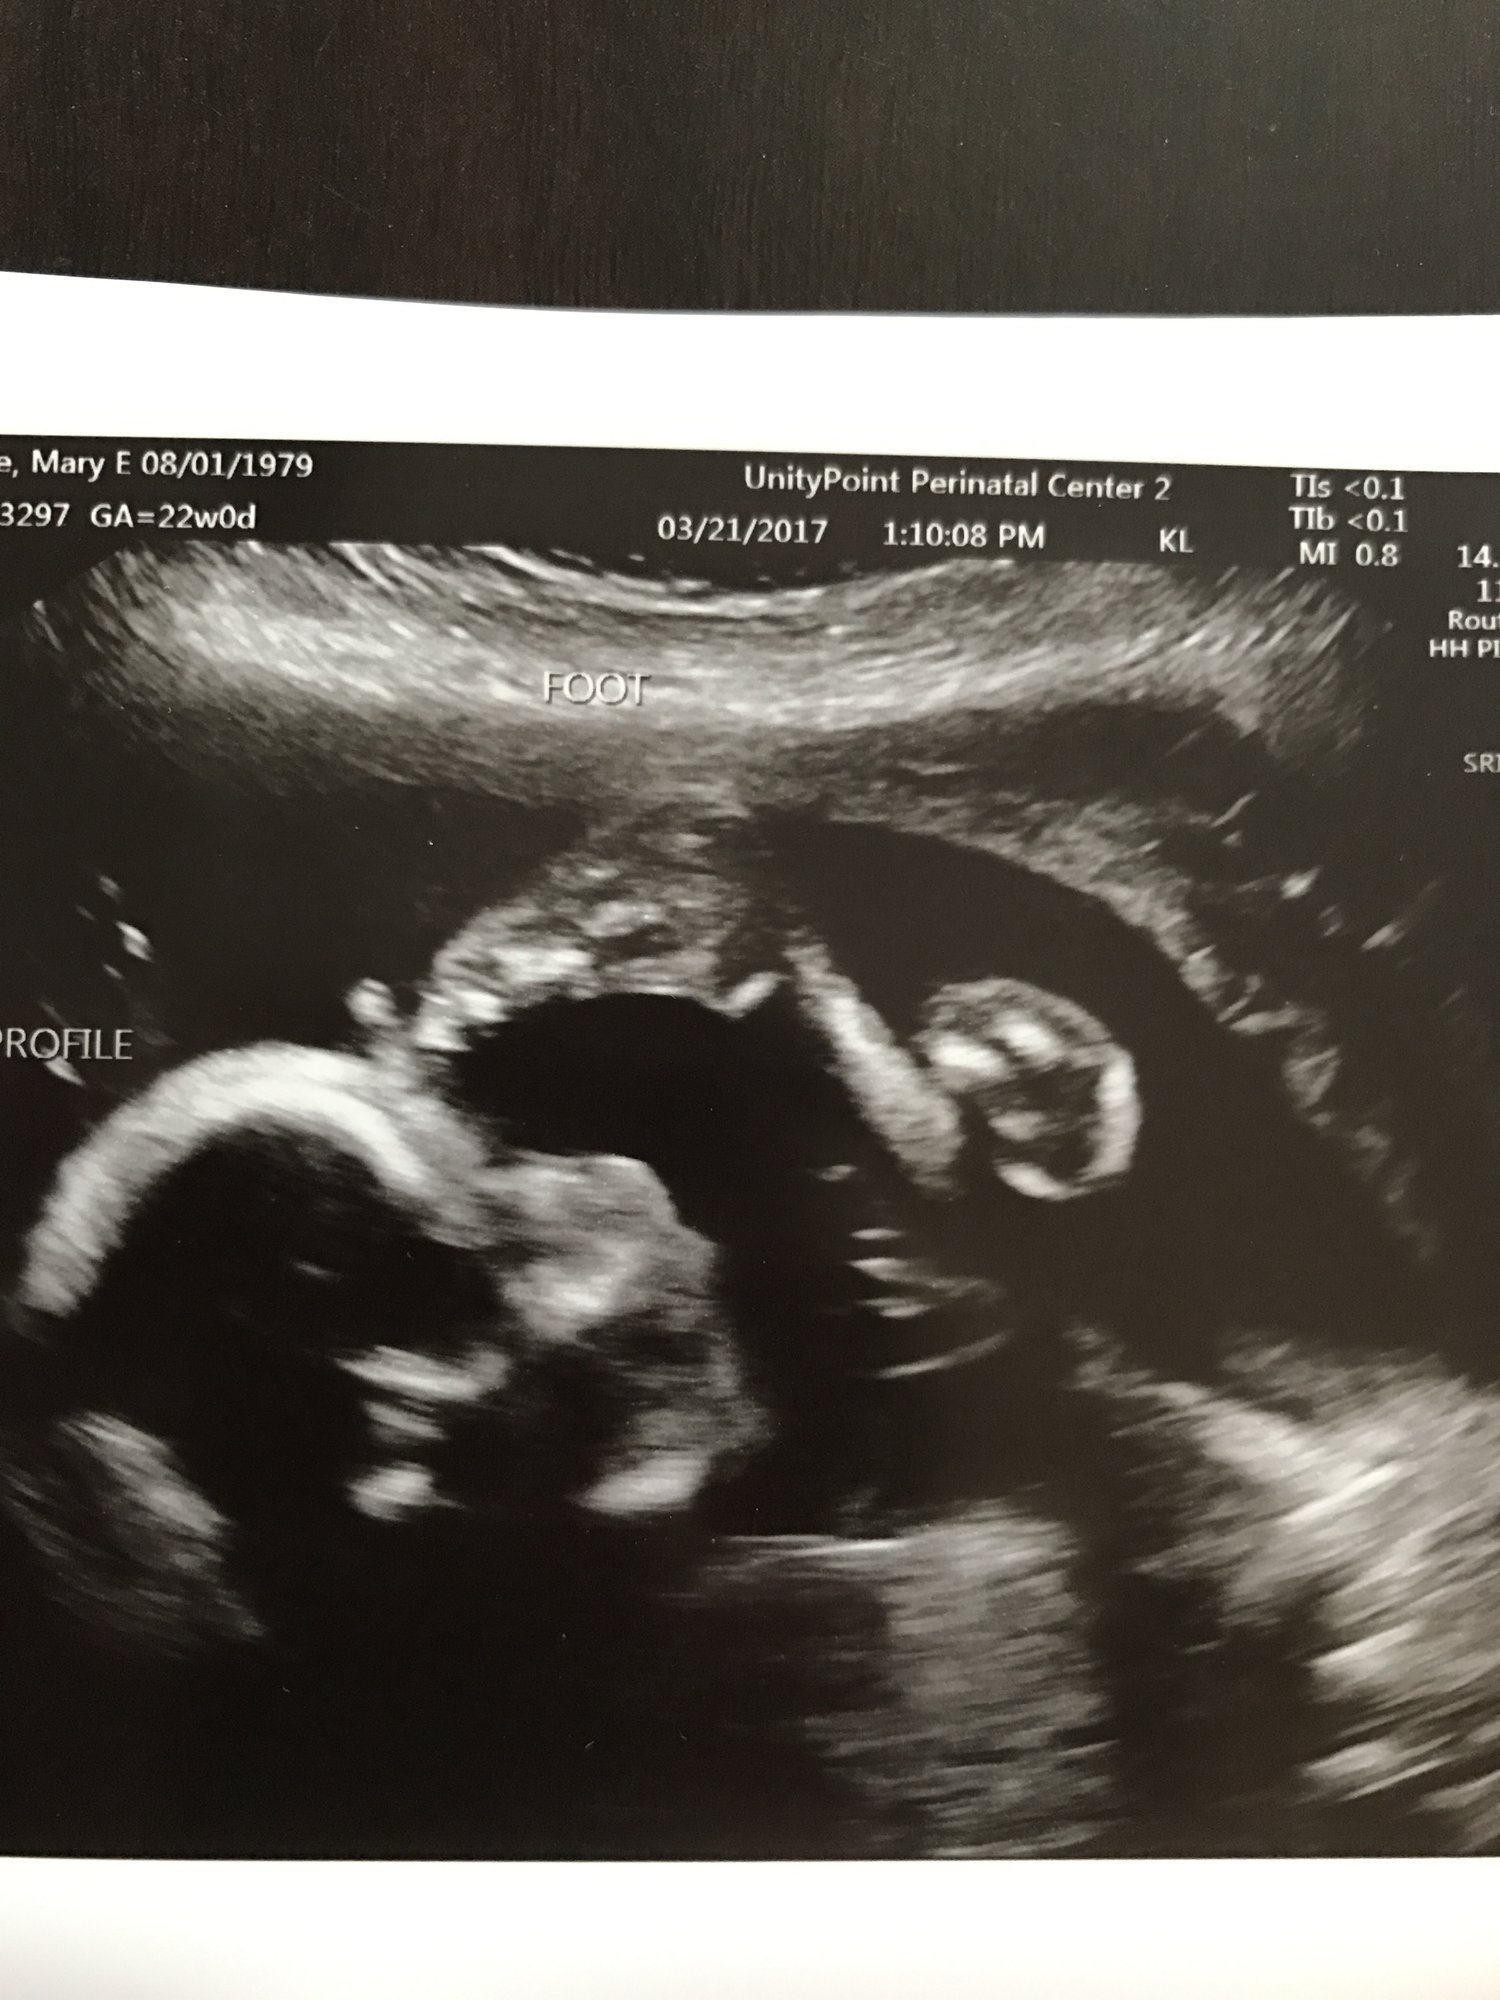

Hi ladies! I had my fetal echo today and they were FINALLY able to get some better pics since Baby B was so uncooperative at our a/s. I have to say this was by far my favorite scan - she even did some 3D shots. Everything looks great which is the most important thing but I'm smiling ear to ear I promised to post a picture if we got them so here you go! Our baby is apparently VERY flexible!